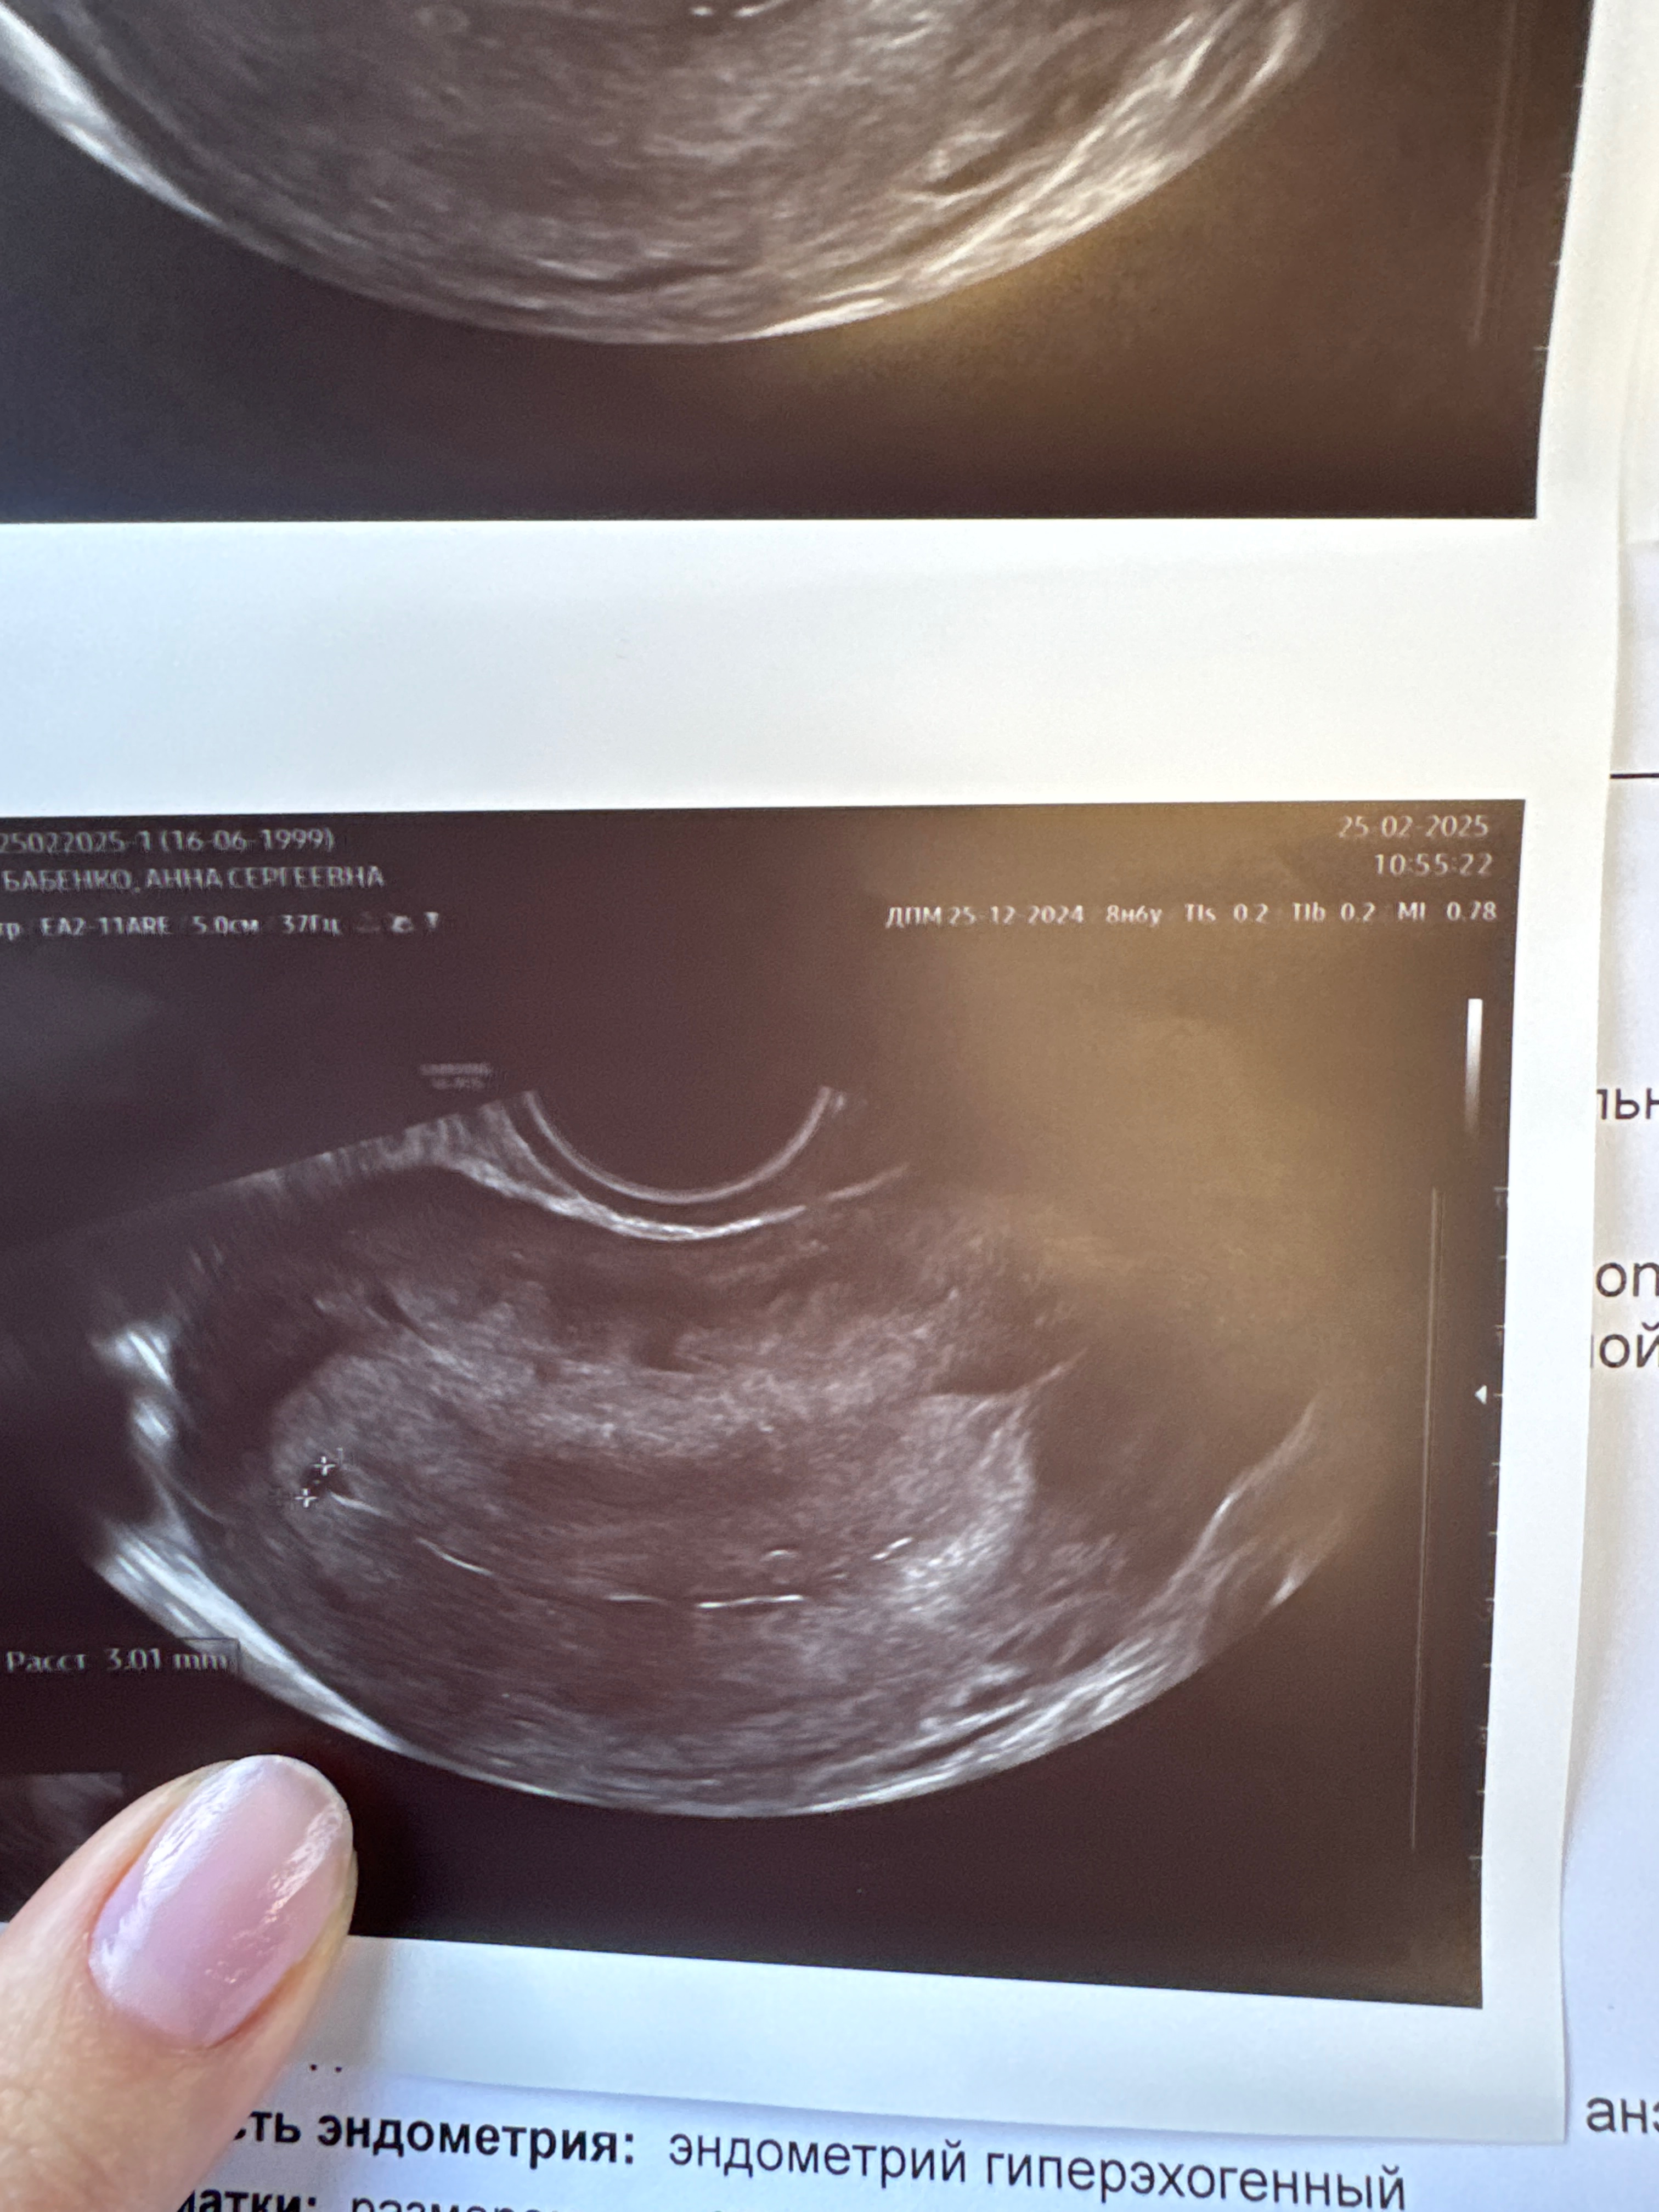

Роза, увидели что - то похожее на ПЯ ещё , но пока не уверенна говорит

У меня тоже подозрение на двойню но срок меньше наверно чем у вас, ходила в понедельник был 4.6 недель акушерских

Пока одно ПЯ, о двойни речь не идет. Дальше что угодно может произойти.

Пока у вас одно пя. Все